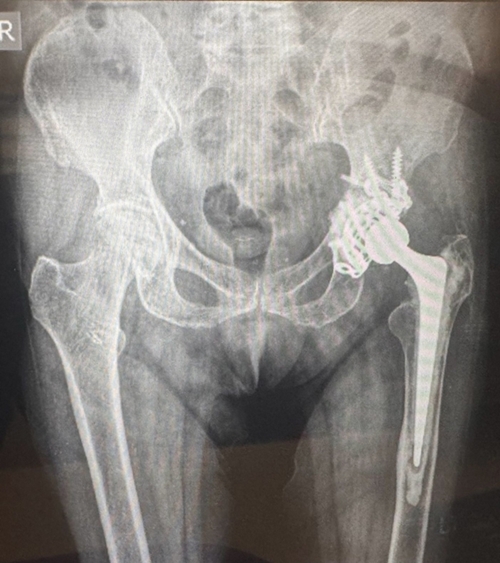

Given the complexity of the case and the patient’s advanced age, the orthopaedic team undertook a detailed clinical assessment and multidisciplinary planning before proceeding with surgery. The surgical team performed a revision total hip replacement using an antiprotrusio cage, a specialised implant designed to reconstruct the hip socket and provide strong structural support when bone strength is compromised.

Dr Atmananda S Hegde, professor and head of the Department of Orthopaedics, said the surgery required careful planning and precise surgical execution. “Managing complex hip revision surgery in a patient of this age requires meticulous planning and a coordinated team approach. In this case, the earlier implant had migrated into the pelvic cavity, making reconstruction technically demanding. By using specialised reconstruction techniques and implants, we were able to restore stability to the hip joint and help the patient regain mobility."